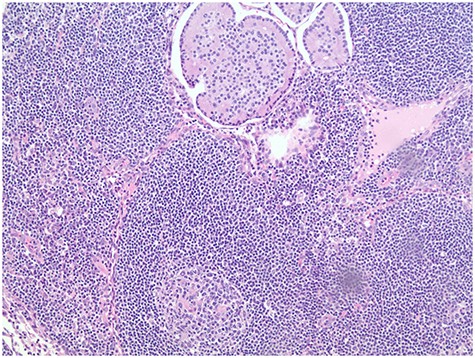

Pathology report revealed the distant umbilical sac was positive for a 2.8-cm metastatic NET (Fig. 3). Four of 19 peripancreatic lymph nodes were positive for metastatic NETs (Fig. 4). Incidental gastrointestinal stromal tumor (GIST) turmorlets less than 1 cm in size were identified in the proximal jejunum (Fig. 5). There was extensive PIN Grade 1–2 found at the pancreatic neck margin and main duct intraductal pancreatic mucinous neoplasm (IPMN) with dysplasia and side branch IPMN (Fig. 6).

Grade 1–2 PIN at the pancreatic neck margin (a); Low power view of main duct IPMN (b).